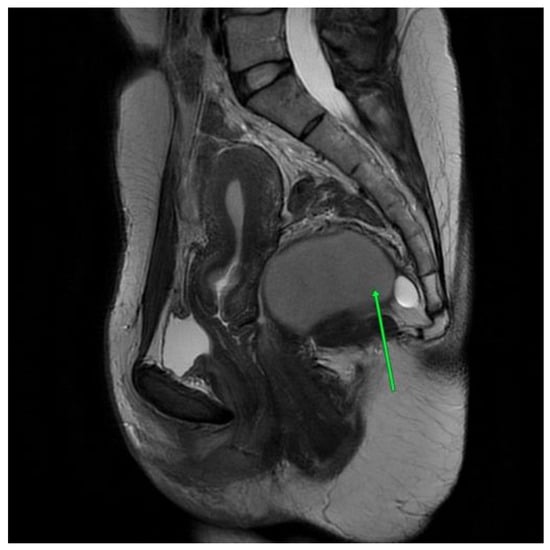

In the histopathological examination, a multilocular, cystic tumor was described. In the wall, fibrous tissue and smooth muscle tissue were visible. Cystic spaces were padded with cuboidal epithelium and stratified squamous epithelium without signs of cell atypia. Malignant transformation was excluded and the tailgut cyst diagnosis was favored [Figure 2].

Figure 2. First patient histopathological examination. (a) Tissue at 4× magnification. (b) Tissue detail at 10× magnification.